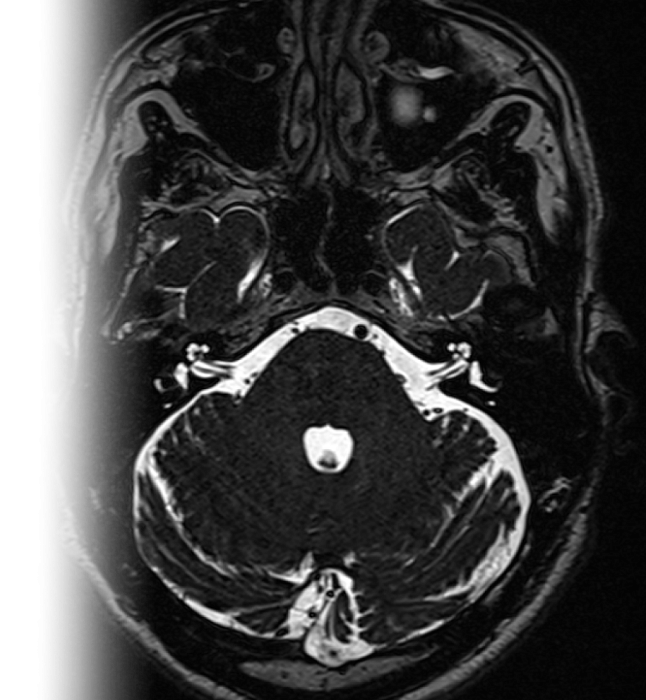

МРТ головного мозга при вазоневральном конфликте (тройничный нерв, вестибулокохлеарный нерв, мостомозжечковый угол) – важный метод исследования, который позволяет оценить структуры мосто-мозжечковых углов, взаимоотношения артерий и черепно-мозговых нервов.

78-1-1-020 МРТ головного мозга при вазоневральном конфликте (тройничный нерв, вестибулокохлеарный нерв, мостомозжечковый угол, запись на диск) 9 800 ₽